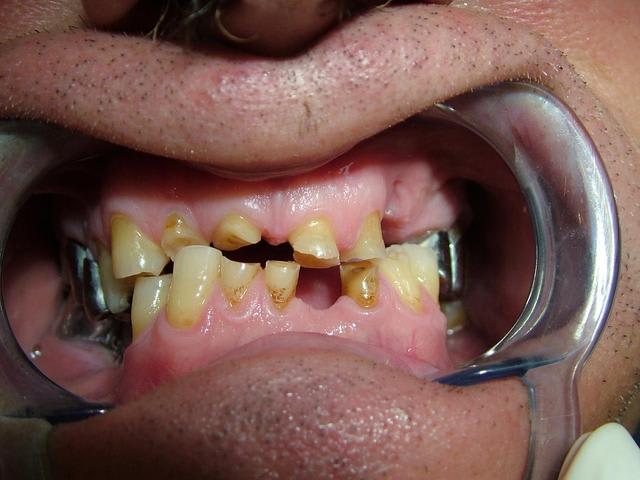

Homme de 57 ans avec DV effondrée.

Contrairement à ce qui a été dit...Il n'y a pas de perte de Dimension verticale. Les secteurs posterieurs sont plus ou moins preservés

Par contre dans le secteur anterieur l'usure des dents à été compensé par une egression qui donne l'illusion de perte de DV...

Le traitement est complexe car on peut pas vraiment augmenter la DV...il y pas ou peu de perte. Si on surevalue la DV, ça peut etre super mal toléré.

Oui...egressé et usée. Regarde l'os alveolaire de la pano.

De toute façon il n'y a pas perte de DV si il n'y a pas perte de calage posterieur...

Je confirme il y a un calage posterieur...presque pas de perte de DV. Donc la distance "maxillo-mandibulaire" n'a pas diminuée.

la mise en occluseur me parait erronée avec ce type d'abrasions les incisives devraient être en contact, mais pas grave l'essentiel c'est l'aperçu. ,

Merci pour toutes les réponses qui m'ont aidé à réfléchir au cas et surtout ne pas me précipiter sur mon plan de traitement stupidement. J'ai revu le patient il y a qq jours et je devais ce jour là lui faire la présentation du plan de traitement. Je lui ai expliqué que son cas était tellment complexe que je n'avais pas pour le moment de solution thérapeutique valable car je n'avais pas encore traité ce type de cas. Le patient a fort bien compris et j'en ai profité pour prendre des radios buccales ; en effet la mise sur occluseur que j'avais sur les précédentes photos était fausse. Le patient "occluse" différement. Voir les nouvelles photos jointes. Il y a très peu de contact antérieur ; j'ai bien demandé une dizaine de fois au patient de se mettre en occlusion pour arriver au même résultat que l'on voit sur les photos. Le patient a bien sur du mal à avoir un occlusion stable.

Ce qui m'interroge le plus c'est comment ce patient est arriver à user le bloc antérieur et arriver à cette situation. Il n'a pas d'habitudes nocives ( ex fumeur de pipes ou autres tics).

Il est vrai que la DV me semble conservé car il y a un calage postérieur côté droit et côté gauche.